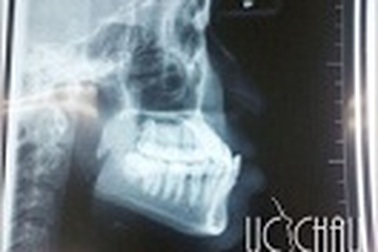

Chỉnh răng hô móm một lần duy nhất tại Thẩm mỹ Úc ChâuChỉnh hình xương hàm dưới chữa móm (hoặc chữa hô), phẫu thuật xương hàm dưới chữa móm (hoặc chữa hô) , phẫu thuật chỉnh nha là một trong những phẫu thuật được nhiều người quan tâm để mang đến vẻ đẹp hoàn thiện trên khuôn mặt.

Phẫu thuật thẩm mỹ hàm hô vẩu (móm)Sự bất cân xứng về hàm trên và hàm dưới gây hô móm, hàm dưới đưa về trước quá mức so với hàm trên gọi là vẩu. Các kỹ thuật chỉnh nha như niềng răng, phẫu thuật cắt xương hàm… là giải pháp tốt nhất để mang lại khuôn mặt đẹp cân xứng hài hòa.